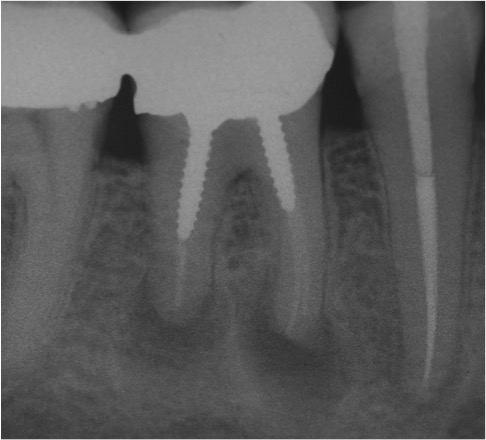

RX pre-operatoria dove si evidenza l’incompleta sigillatura dei canali di un molare inferiore di sinistra e la presenza di granuloma nella radice distale.

Successivamente la radiografia a 1 anno di distanza dal ritrattamento endodontico che mette in risalto la perfetta sigillatura dei canali e la scomparsa del granuloma.